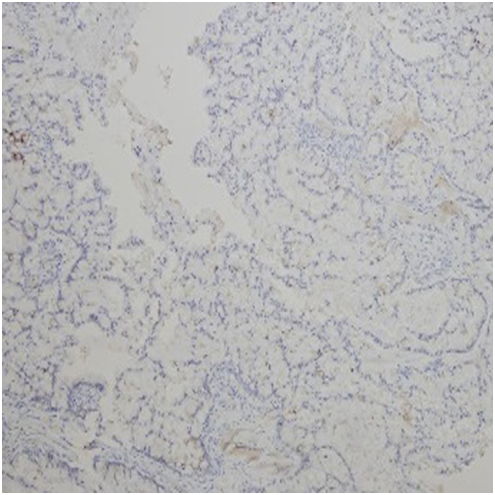

A seventy-five year old male patient referred to our clinic for dyspnea and involuntary weight loss. He was an active smoker for one hundred thirty packets/year, he had not asbestos exposure. Patient was hospitalized to our clinic for pleural effusion and infection six months ago and no malignancy was detected in Thoracic CT and fluid cytology. The patient whom fluid was lowered with ant biotherapy was discharged at the end of the treatment so as to come to the control. Massive effusion was determined in the left hemithorax in the patient who reapplied on the increase of symptoms. Irregular FDG uptake was present in the areas of common linear nodular thickening in the left hemi thorax pleura on PET/CT (SUV max 7.2-11) (Figure 5). Tumor cells composed of invasive glandular structures in the pleura and with mucinous material in cytoplasm were detected as a result of VATS. The tumor is negative in the pleural fluid. CK8/18, CD15, CEA, CK7 was positive and D2-40, calretinin; WT-1, TTF-1 and CK-20 were negative in immunohistochemical staining (Figure 6). Chemotherapy was started to the patient who was diagnosed with invasive mucinous adenocarcinoma.

Figure 6 Invasive mucinous adenocarcinoma. Calretinin (-) in tumor cells with immunohistochemical stainingx100.